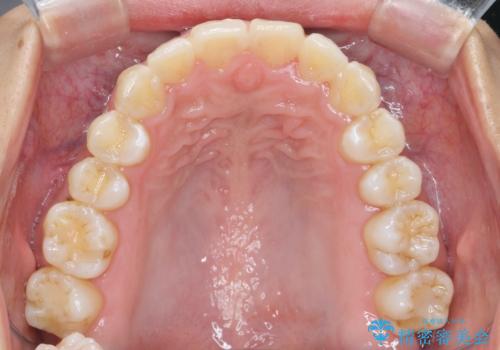

出っ歯感のある前歯を治したい、抜歯をしないマウスピース矯正

- 前歯のガタつき、突出感のある前歯の改善を求めて来院されました。

前歯の角度を改善し審美性を高めるとともに、奥歯のガタつきも並べ直すことで安定した咬合関係の確立を目指します。

歯列の側方拡大をしっかりと行ったことで歯を抜かずに前歯の角度をしっかりと改善することができました。